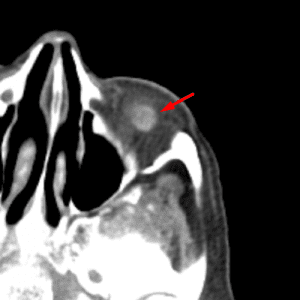

Calcific Scleral Plaques

Mimicking a foreign body